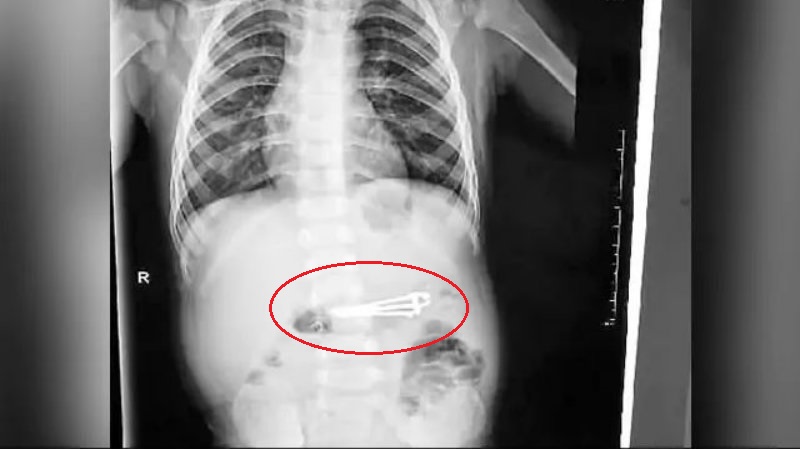

ಮಗು ನೈಲ್ ಕಟ್ಟರ್ ನುಂಗಿದ ತಕ್ಷಣವೇ ನಗರದ ಮಕ್ಕಳ ಆಸ್ಪತ್ರೆಗೆ ದಾಖಲಿಸಲಾಗಿದೆ. ನಂತರ ವೈದ್ಯರು ಎಂಡೋಸ್ಕೋಪಿ ಮೂಲಕ ಮಗುವಿನ ಹೊಟ್ಟೆಯೊಳಗೆ ಸೇರಿದ್ದ 2.4 ಇಂಚಿನ ನೈಲ್ ಕಟರ್ ನ್ನು ಹೊರ ತೆಗೆದಿದ್ದಾರೆ. ಸದ್ಯಕ್ಕೆ ಮಗು ಪ್ರಾಣಾಪಾಯದಿಂದ ಪಾರಾಗಿದ್ದು, ಆರೋಗ್ಯವಾಗಿ ಮನೆಗೆ ಹಿಂದಿರುಗಿದೆ.